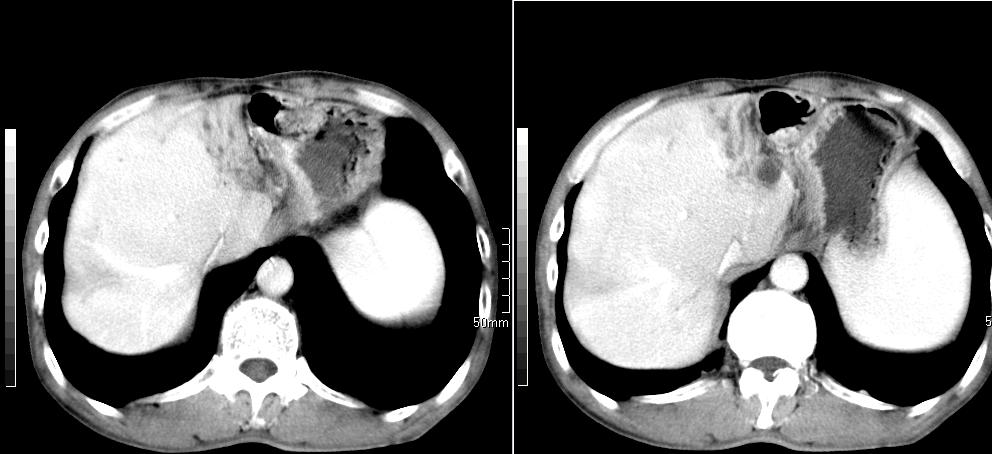

标题: CT26769:男,58岁,腹胀、腹部不适一年余 [打印本页]

标题: CT26769:男,58岁,腹胀、腹部不适一年余

肠系膜脂膜炎,胆囊炎,脾大。建议结合临床。鉴别:慢性胰腺炎并假囊肿形成。

1 慢性胰腺炎并假囊肿形成。2 慢性胆囊炎并累及肝边缘!

1)考虑慢性胰腺炎并假性囊肿形成。2) 慢性胆囊炎。3)肝内胆管扩张。

支持1 慢性胰腺炎并假囊肿形成。2 慢性胆囊炎。

1肝内胆管扩张,性质待定,2慢性胰腺炎胰管扩张,胰腺颈部假囊肿,3肝左叶低密度为小囊肿,4胆囊炎。